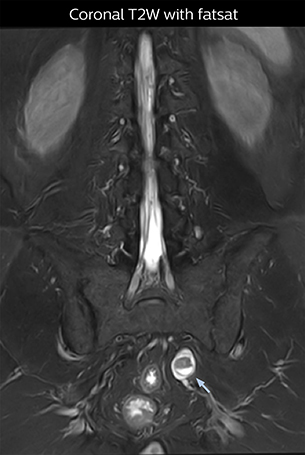

“For example, in sagittal images, when the presence of fat is observed in the intervertebral foramen, it suggests that there is a margin around the nerve. Similarly, the absence of fat indicates that the nerve is being compressed. So, we used to deduce nerve compression indirectly. With NerveVIEW, however, we can observe the condition of the nerves directly, regardless of the presence or absence of fat. We always prefer such direct observation of anatomy over having to make an inference about it.”

“Although symptoms of typical disc herniation and atypical hernia are very similar, the actual site of herniation is different. It is therefore important to characterize the nerve’s condition both inside and outside of the intervertebral foramina. “Conversely, if we see no abnormality in NerveVIEW, we can assume at least that there is no severe condition that requires surgery. Like this, it can help us avoid unnecessary surgery. NerveVIEW can have a tremendous impact in this way.”

“NerveVIEW is really useful for those cases where a nerve disorder is strongly suspected based on the clinical examination but our regular MRI images do not show any findings. These atypical herniations and spinal canal stenosis, occurring in 5% to 15% of the total lumbar herniation/stenosis cases are our main target when using NerveVIEW,” says Dr. Yabuki.

“The intra-luminal signal of veins, especially around the intervertebral space, can be suppressed well with NerveVIEW. As a result, we can easily observe the detailed nerve structure around the posterior ganglion,” he says. “This is why we use 3D NerveVIEW for intraforaminal stenosis and extraforaminal stenosis/herniation (lateral disc herniation). On the other hand, if herniation is suspected to exist inside the dorsal root ganglion (DRG), balanced TFE or ProSet-FFE is applied. NerveVIEW is not suitable for evaluating the median type of herniation.” The SE-EPI DWI-based method for MR neurography works well for large FOV exams like whole-body MRI, but focal examination of nerves is often limited by the attainable spatial resolution (both inplane and slice direction) and geometric distortion. “3D NerveVIEW achieves higher in-plane resolution – close to our other routine spine sequences – and the source images can be used instead of adding a fat-suppressed T2-weighted sequence,” Tanji says.